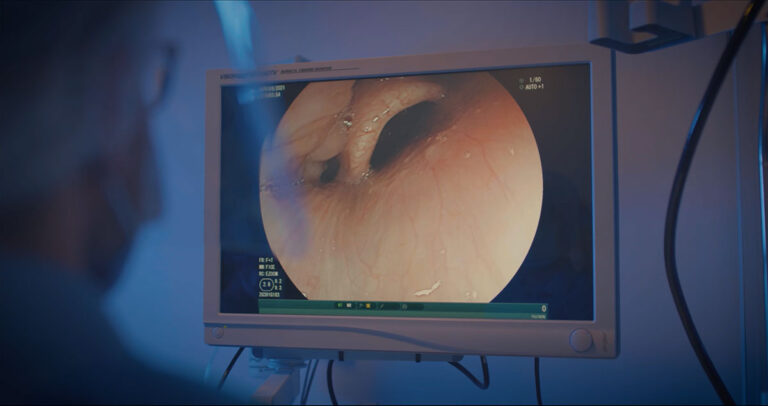

Imagine realizar procedimentos cirúrgicos e endoscópicos no seu próprio espaço, agregando valor real à sua prática e entregando aos seus pacientes uma experiência de alto padrão. Essa mentoria é para quem quer sair da estagnação e construir um verdadeiro Hospital-Dia do Aparelho Digestivo – seja você um profissional já consolidado ou um especialista em início de jornada, pronto para empreender com propósito.

Implementar um programa completo de Cirurgia Ambulatorial e Endoscopia Terapêutica.

Ampliar seu portfólio com novos exames e procedimentos.